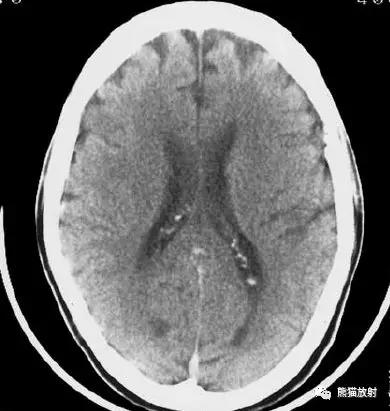

左侧尾状核头脑梗死;右侧外囊腔隙性脑梗死。

右侧豆状核梗死灶(发病后15d),明显均匀强化。另左侧丘脑见腔隙性梗死灶。